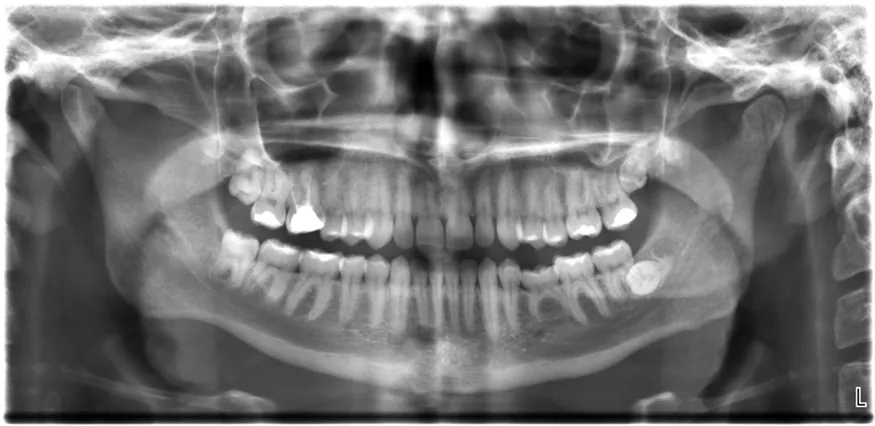

The X-ray image of front view of the jaw, especially the teeth.

Figure 30.24 An x-ray image reveals fillings in a person’s teeth. (credit: Dmitry G, Wikimedia Commons)

All of us can identify diagnostic uses of x-ray photons. Among these are the universal dental and medical x rays that have become an essential part of medical diagnostics. (See Figure 30.25 and Figure 30.26.) X rays are also used to inspect our luggage at airports, as shown in Figure 30.24, and for early detection of cracks in crucial aircraft components. An x ray is not only a noun meaning high-energy photon, it also is an image produced by x rays, and it has been made into a familiar verb—to be x-rayed.

The most common x-ray images are simple shadows. Since x-ray photons have high energies, they penetrate materials that are opaque to visible light. The more energy an x-ray photon has, the more material it will penetrate. So an x-ray tube may be operated at 50.0 kV for a chest x ray, whereas it may need to be operated at 100 kV to examine a broken leg in a cast. The depth of penetration is related to the density of the material as well as to the energy of the photon. The denser the material, the fewer x-ray photons get through and the darker the shadow. Thus x rays excel at detecting breaks in bones and in imaging other physiological structures, such as some tumors, that differ in density from surrounding material. Because of their high photon energy, x rays produce significant ionization in materials and damage cells in biological organisms. Modern uses minimize exposure to the patient and eliminate exposure to others. Biological effects of x rays will be explored in the next chapter along with other types of ionizing radiation such as those produced by nuclei.